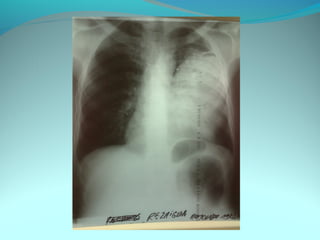

Opacité triangulaire a base cardiaque a sommet

axillaire dense et homogène

Par ailleurs on note

Une opacité plus dense que celle arrondie de 3cm de

diam hilaire gauche ;une surélévation de la coupole

diaphragmatique gauche é poche a aire gastrique

DIAGNOSTIC :

ADP hilaire gauche avec trouble de ventilation

Surelevation de la coupole G et de la poche gastrique

avec de clarté le médiastin

DIAGNOSTIC:

Hernie diaphragmatique paralysie du diaphragme